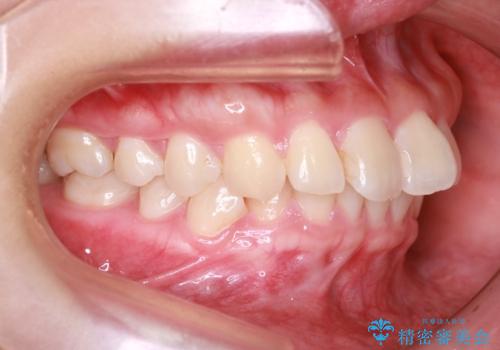

- 前歯の捻れと口元の突出を主訴に来院されました。

インビザラインを用いて上顎の遠心移動を行い、前歯を下げながら凸凹を綺麗に治すことができました。

歯を抜かない矯正治療を行う場合、口元は極端には変わりません。

今回は奥歯の遠心移動を行い、できる限り前歯を下げられるように治療を行いました。